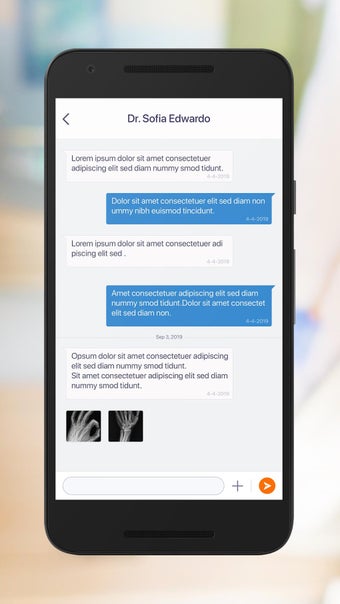

Một trong những tính năng quan trọng nhất của ứng dụng là việc truy cập dữ liệu y tế một chạm dễ dàng. Bệnh nhân có thể truy cập dữ liệu y tế của mình hoặc dữ liệu đại diện gia đình một cách an toàn và nhanh chóng, làm cho nó trở thành một công cụ tuyệt vời để quản lý lịch sử bệnh án của họ. Ứng dụng cũng cho phép người dùng tìm kiếm các phòng khám và bệnh viện gần đó, lên lịch hẹn, và thậm chí nhận chỉ đường đến cuộc hẹn của họ qua Uber. Ngoài ra, bệnh nhân có thể giao tiếp với nhà cung cấp chăm sóc của họ qua tin nhắn an toàn, chia sẻ hình ảnh y tế và cho phép thành viên gia đình truy cập dữ liệu y tế của họ thông qua cài đặt proxy an toàn. Cuối cùng, ứng dụng cung cấp tài liệu giáo dục liên quan đến chăm sóc sức khỏe và có thể kết nối với các thiết bị đeo được hoặc nhập dữ liệu y tế thủ công.